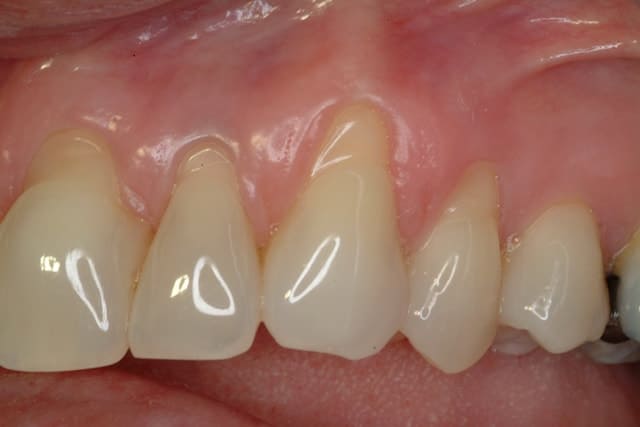

After

Patient: Jill